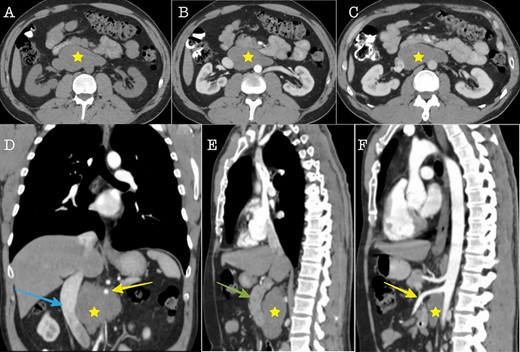

A 43-year-old Caucasian male with an unremarkable past medical history was referred for a retroperitoneal tumor diagnosed on a computerized tomography (CT) scan performed for progressively worsening lower back pain. Physical examination was unremarkable and the laboratory values including tumor markers were within normal range. The abdominal CT scan demonstrated a large solid non-enhancing retroperitoneal mass, with a well-defined margin, measuring 9.6 cm × 9.3 cm, located anteriorly to the aorta and displacing the inferior vena cava (IVC), pancreas, the superior mesenteric artery (SMA) and the renal vessels (Fig. 1). Patient underwent an exploratory laparotomy and a tumor was found lying in the retroperitoneum adherent to aorta, IVC, SMA, pancreas and renal vessels (Fig. 2). Complete right medial visceral rotation was performed and the small bowel mesentery was mobilized exposing the retroperitoneum. Meticulous dissection of the tumor from the aorta IVC and their main abdominal branches was performed and the specimen was excised. The specimen consisted of a well-circumscribed, solid tan to yellow tumor measuring ~9 × 9 cm encased by a fibrous capsule. Histological, no atypia or mitotic activity was evident and the tumor was composed of variably sized mature ganglion cells with satellite cells deposited in a neuromatous stroma. All three lymph nodes included within the surgical specimen were not infiltrated. The ganglion cells stained positive for S-100 protein, glial fibrillary acidic protein and neuron-specific enolase (NSE) while Ki-67 labeling index was <1% (Fig. 3). The final pathology report was RGN. Postoperative course was uncomplicated. Patient is well on a 2-years follow-up without clinical or radiographic evidence of recurrent disease.

Cross sectional imaging (A): Axial CT without contrast medium, (B) Axial CT contrast-enhanced, arterial phase, (C) Axial CT, contrast-enhanced, portal venous phase. The images show a large solid retroperitoneal mass (yellow star) isoattenuating to the muscles, without contrast enhancement. (D) Coronal reconstruction and (E, F): Sagittal reconstructions demonstrate the anatomic relationships of the mass with IVC (blue arrow), superior mesenteric artery (yellow arrow) and pancreas (green arrow). The mass is located dorsally to the pancreas, encases the superior mesenteric artery and displaces the IVC to the right.